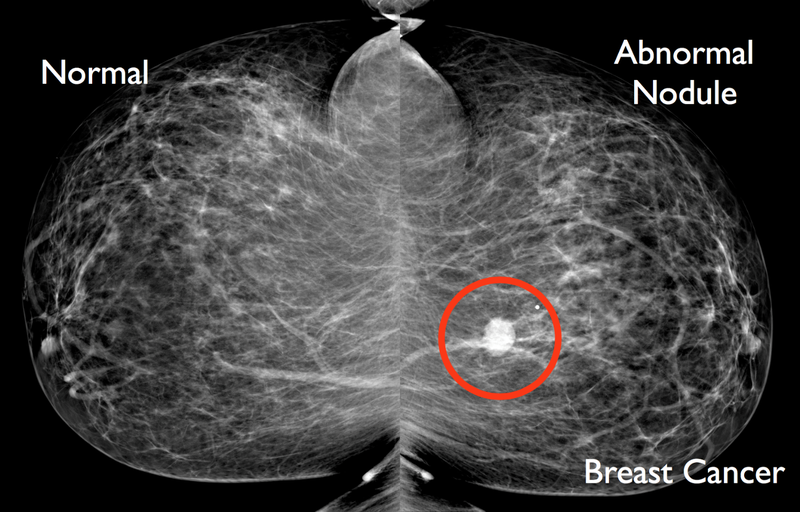

Chụp X-quang tuyến vú là cách chắc chắn nhất để biết có bị ung thư vú hay không?

Sai. Trên thực tế, chụp X-quang tuyến vú thực sự bỏ sót một tỷ lệ nhỏ khoảng 10 – 20% trường hợp ung thư vú. Đây thường là do kết quả của tổ chức mô vú dày đặc. Vú có tổ chức mô càng dày đặc thì khả năng ung thư bị mô vú che giấu càng cao. Điều này càng cho thấy vai trò của chụp X-quang tuyến vú thường xuyên trở nên quan trọng hơn.

Ngay cả khi bạn có kết quả chụp X-quang tuyến vú bất thường, thì cũng không chắc chắn rằng đó là ung thư. Khi đó, sinh thiết được thực hiện để xác định xem sự bất thường đó có phải là ung thư hay không.

Tuy nhiên, bất chấp những điều trên, chụp X-quang tuyến vú vẫn là cách hiệu quả nhất để phát hiện sớm ung thư vú, vì nó có thể phát hiện các khối u nhỏ trước từ 2 - 3 năm, cho tới khi có thể sờ thấy khối u, cục đó.